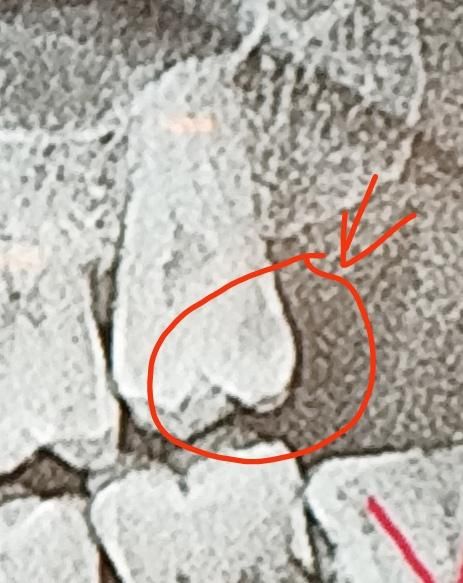

치아 엑스레이 사진에서 동그라미 친부분 충치인가요?

사진은 위 왼쪽 끝 어금니 치과두곳 엑스레이 사진인데요 동그라미친부분에 약간 검은 부분이 있는데 통증은 아직 없고 잘닥고는 있는데 이거 치료받아야할 충치인가요? 아님 그냥 내비둬도되나요?

• 1번 째 사진